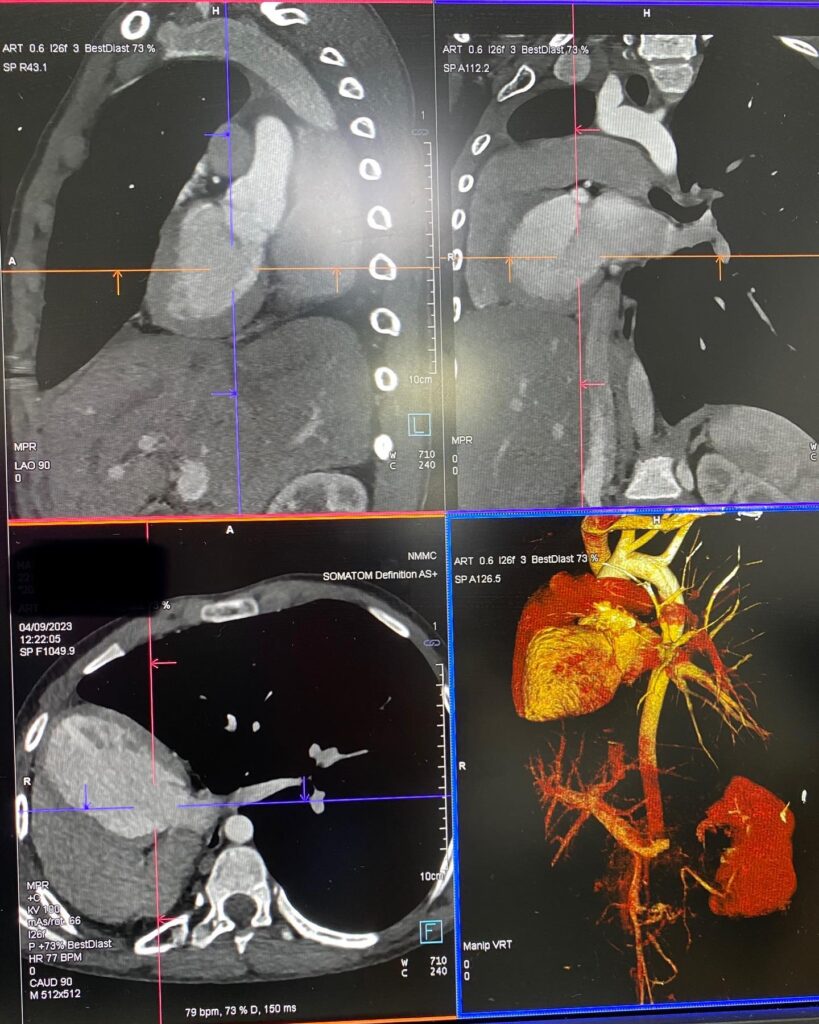

««Նորք-Մարաշ» բժշկական կենտրոն դիմելիս 14–ամյա տղայի գանգատը եղել է աջ կողմից սրտխփոցի զգացումը (մայրիկի խոսքերով՝ երեխան դա նկատել է դեռ 1 տարի առաջ ֆուտբոլ խաղալիս)։ Էխոսրտագրության ժամանակ երեխայի սիրտը աջից էր, սակայն դա սովորական դեկստրակարդիա չէր, ինչը բժշկի մոտ կասկած առաջացրեց, որի կապակցությամբ կատարվեց կրծքավանդակի կոնտրաստ համակարգչային տոմոգրաֆիա։

Արդյունքը տպավորիչ էր։ Երեխայի մոտ առկա էր աջ թոքի ագենեզիա (թոքը չի զարգացել, համապատասխանաբար բացակայում էին նաև աջ գլխավոր բրոնխը, աջ թոքային զարկերակը և աջ թոքային երակները), ինչի հետևանքով միջնորմը (այդ թվում սիրտը) տեղակայված է կրծքավանդակի աջ կեսում։ Սրտի նման տեղակայումը հեմոդինամիկ շեղումներ չի առաջացրել. երեխան ունի կառուցվածքային առողջ սիրտ։ Երեխան ուղեգրվել է թոքաբանի և օրթոպեդի խորհրդատվության, իսկ «Նորք-Մարաշ» ԲԿ-ում կլինի դինամիկ հսկողության տակ»,- հայտնում են «Նորք-Մարաշ» ԲԿ-ից։